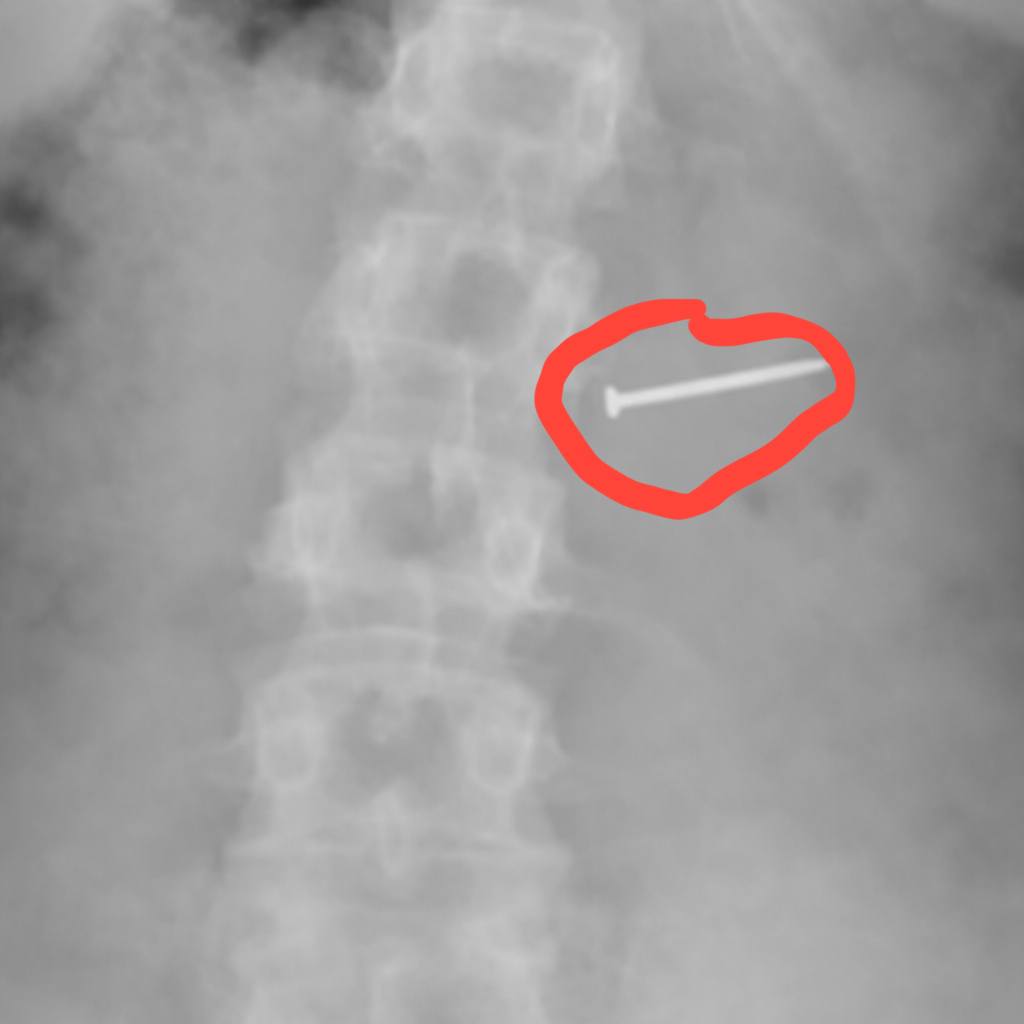

Din precauție, Buckley a mers la spital pentru o radiografie, iar testele au confirmat că înghițise un cui.

În aceeași seară, medicii i-au făcut o endoscopie și au descoperit „două fragmente metalice” care s-au fixat în intestinele ei. După o intervenție chirurgicală intestinală pentru îndepărtarea corpurilor străine, Buckley a declarat că a dezvoltat un cheag de sânge, care a dus la o ablație.